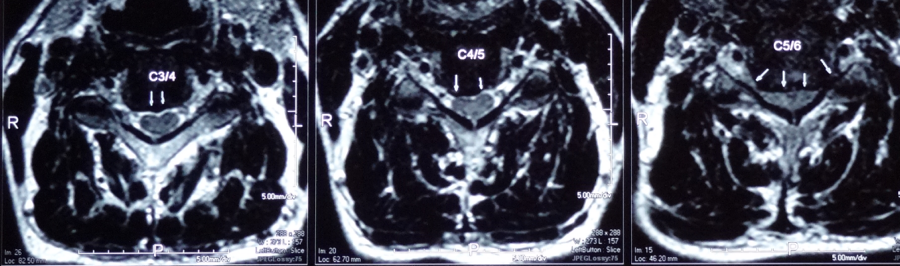

頸椎椎間盤最常見受壓的頸椎關節是頸椎第5節和第6節(C5,6),一般從X光片中可看見椎節之間的空隙變少,椎骨有退化跡象。除頸椎第5節和第6節之外,還有頸椎第3節和第4節(C3,4),亦是受壓較大的部位,而受壓對其他椎節的變化,亦隨之而來。

除頸椎第5節和第6節之外,還有頸椎第3節和第4節(C3,4),亦是受壓較大的部位,而受壓對其他椎節的變化,亦隨之而來。